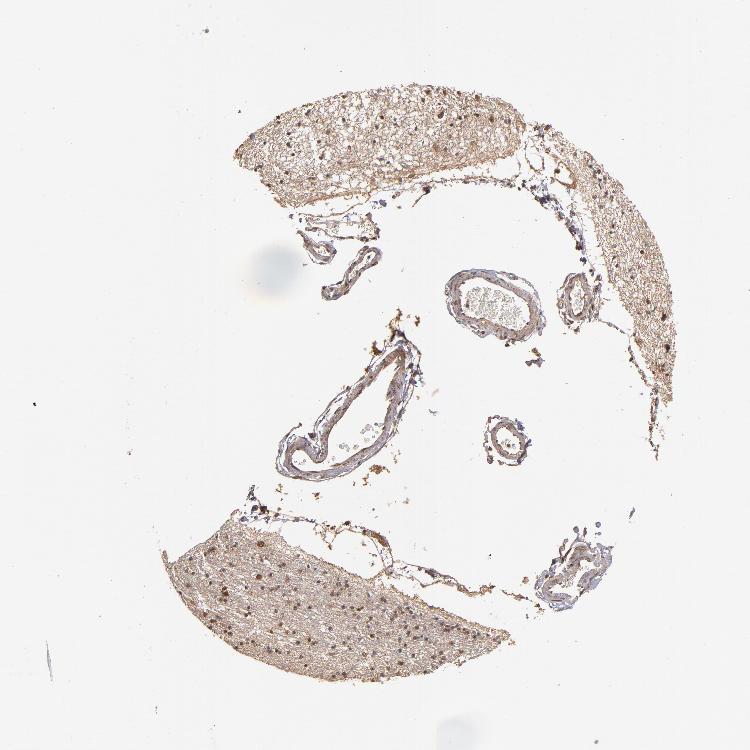

HIPPOCAMPUS - Antibody stainingi

Antibody staining in the annotated cell types in the current human tissue is reported as not detected, low, medium, or high, based on conventional immunohistochemistry profiling in selected tissues. This score is based on the combination of the staining intensity and fraction of stained cells.

Each image is clickable and will lead to virtual microscopy that enables deeper exploration of all samples and also displays staining intensity scores, fraction scores and subcellular localization as well as patient and tissue information for each sample.

Antibody HPA002185Antibody CAB017787

Glial cells MediumLow

Neuronal cells HighLow